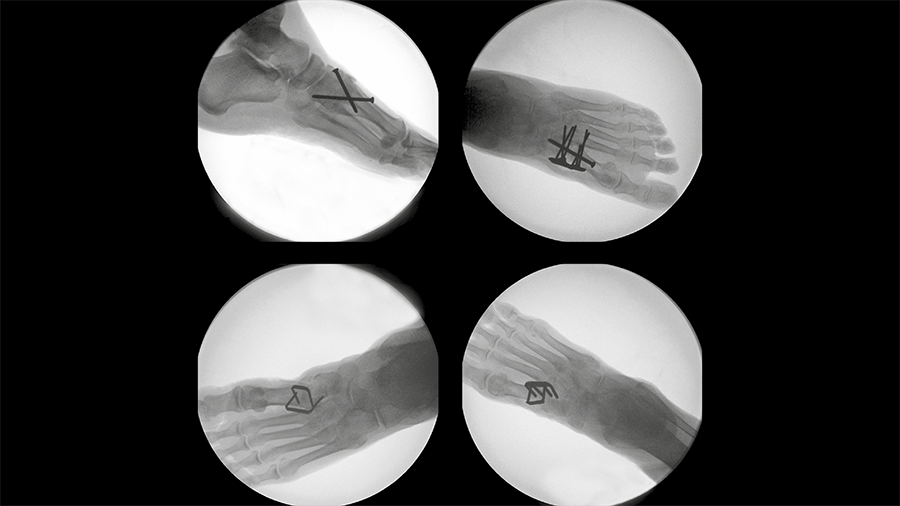

The DPS Hammertoe CCI has a staple-like design with four legs and a low profile connecting bridge (Fig 1). It is made of biocompatible Nitinol, a metal alloy of nickel and titanium, which is known for its superelastic properties and shape memory behavior.

Once the DPS Hammertoe CCI is inserted into the bone and released from the Insertion Stick, the implant attempts to regain its original shape with converging legs thereby providing active continuous compression at the fusion site (Fig 4). The design with the four legs orthogonal to the bone axis and the active compression feature are beneficial for the distraction resistance (Fig 5).